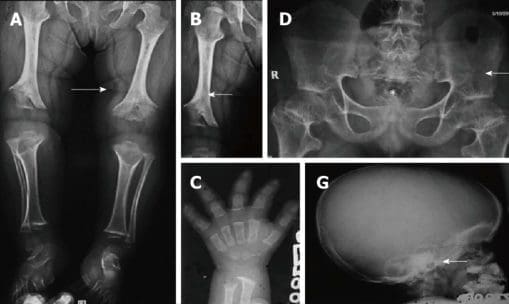

Achondroplasia can be detected before birth through the use of prenatal ultrasound. Moreover, a DNA test can also be performed to identify homozygosity, where two copies of the gene are inherited causing the deadly condition resulting in stillbirths. Clinical features include megalocephaly, short limbs, prominent forehead, thoracolumbar kyphosis and mid-face hypoplasia. Complications such as dental malocclusion, hydrocephalus and replicated otitis media may also develop. The risk of death in infancy may be increased as a result of the probability of compression of the spinal cord with or without upper airway obstruction.